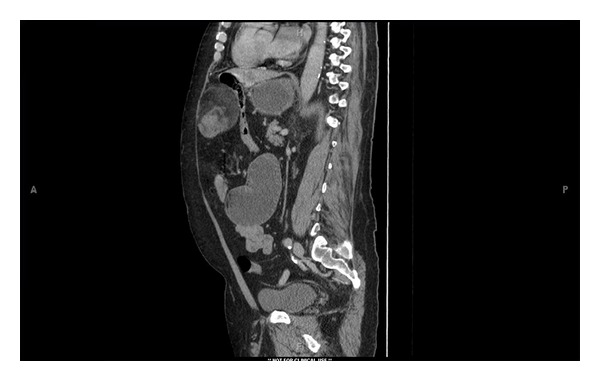

Figure 3.

Computed tomographic sagittal image showing anterior epigastric mass compressing distal small bowel, causing dilated duodenum and stomach proximally.